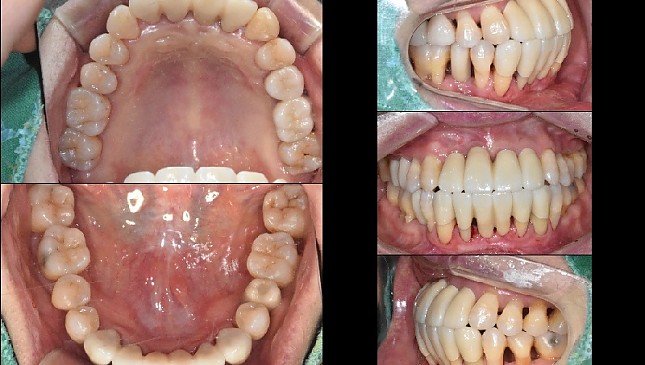

치아살리기 치료 전후 사진

잇몸재생교정 치료 전후사진

잇몸 전체가 무너져 동시다발적으로 죽어가던 치아들을 한꺼번에 살려 냅니다.